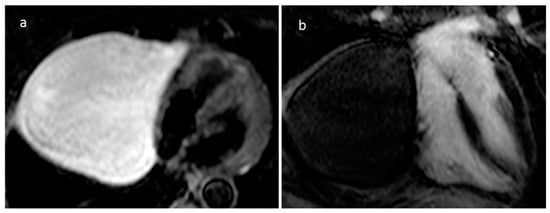

3.10. Hematoma

| Hematoma | Usually adulthood, previous surgery, traumatic heart injury, coagulopaty, anticoagulants | Pericardium | Usually, asymptomatic | Previous cardiac surgery, mass near surgical site or clips, usually well-defined borders. Usually absent contrast-enhancement | Acute phase: echo-lucent Chronic phase: mass like and echogenic | Heterogeneous, clips, hyperdense in acute phase, density decrease in chronic phase, calcific components in chronic hematoma | Acute: hyper T1w and T2w Subacute: heterogeneous with hyper T1 and T2w areas Chronic: hypo T1w and T2w with dark peripheral rim. No internal enhancement, possible rim enhancement |